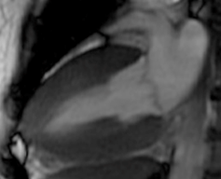

心臓MRI

MRI(磁気共鳴画像診断法:Magnetic Resonance Imaging)は、強力な磁石と電磁波を用いて、身体各所の断層像を観察できる検査です。

心筋の壁運動の評価や心筋の繊維化(ダメージを受けた部位)の評価を行います。